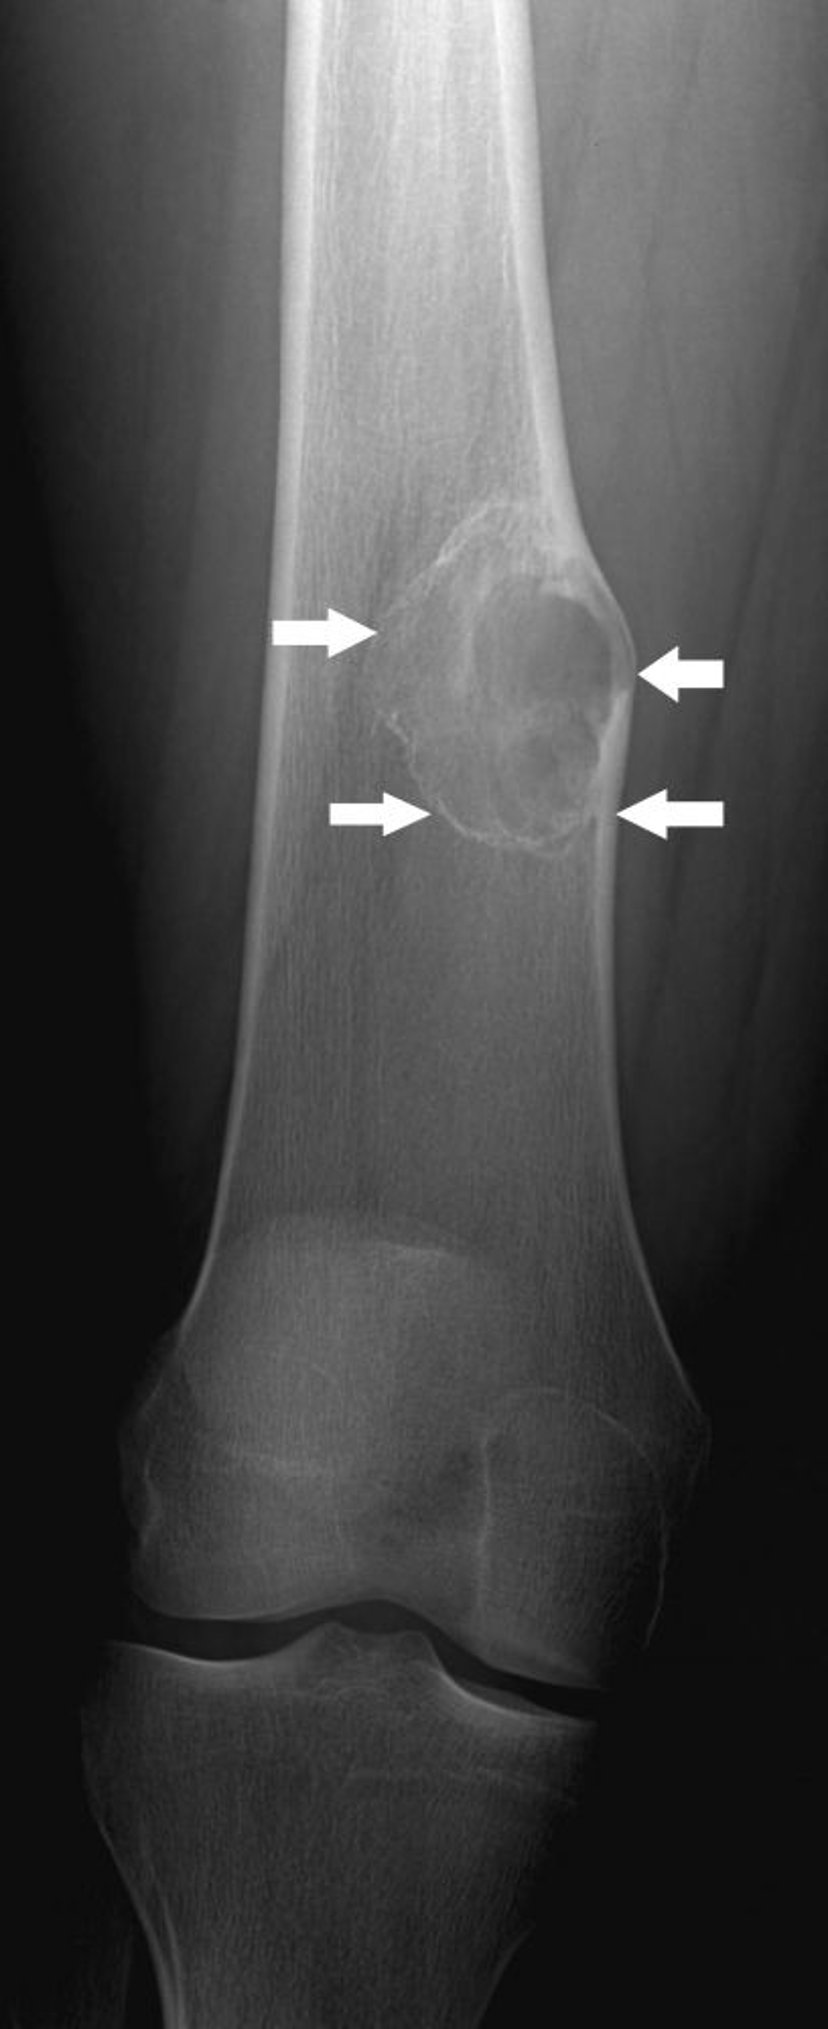

Radiografia che mostra un fibroma non ossificante (frecce) del femore sopra al ginocchio.

Per gentile concessione di Michael J. Joyce, MD e Hakan Ilaslan, MD.